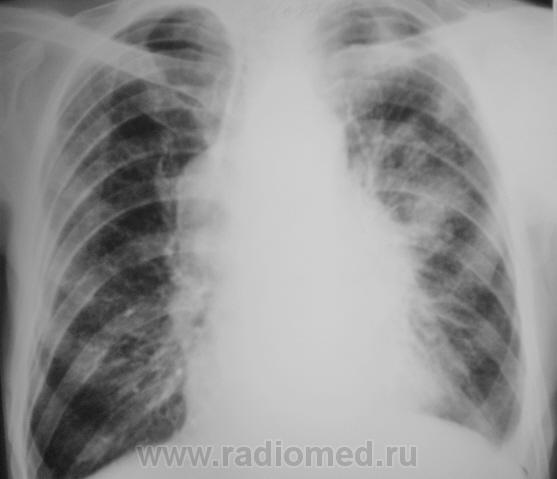

Отдельные снимки этого пациента выставлялись на сайте, но мы никогда не имели полного "набора", так как рентгенологические исследования проводились в трех ЛПУ - у нас и в двух ЛПУ областного уровня (спец. ЛПУ), где пациент получал специфическое лечение. Сегодня, мы имеем полный набор снимков, и мне показалось целесообразным выставить, именно, динамику....

Пациент был взят на контроль в 2009 году, было произведено дообследование в виде томографии в стандартных срезах, был заподозрен очаговый туберкуулёз, который был подтвержден " в области" и пациент был взят на учет. Было назначено специфическое лечение.

После проведения данного исследования возникло подозрение, что "это" не туберкулёз, или имеет место сочетанная патология.

После первой госпитализации в областном спец. ЛПУ, при выписке, в виде контроля динамики, была сделана рентгенограмма в прямой проекции, которая, на мой взгляд, имеет определенный интерес.

В последнее время пациент затежелел и был госпитализирован в областное ЛПУ, где было проведено несколько исследований.

Ответы есть. Пациенту выставлена "четверка". Проведено шесть курсов "химии".

С учетом срезы 11 см (снижение прозрачности легочной  ткани в медиальных отделах верхушечных сегментов), нами динамика была оценена, как "отрицательная.

ФБС была сделана в областном учреждении.

Томография гортани была также произведена в "области". ЛОРами был взят материал для биопсии.

Все это было не в нашем ЛПУ - ЦРБ, а в областной туббольнице. Знаю только, что после биопсии диагноз был изменен, биопсия была также из лимфоузлов,  да и пациенту сильно похужело, сейчас уже не встает...